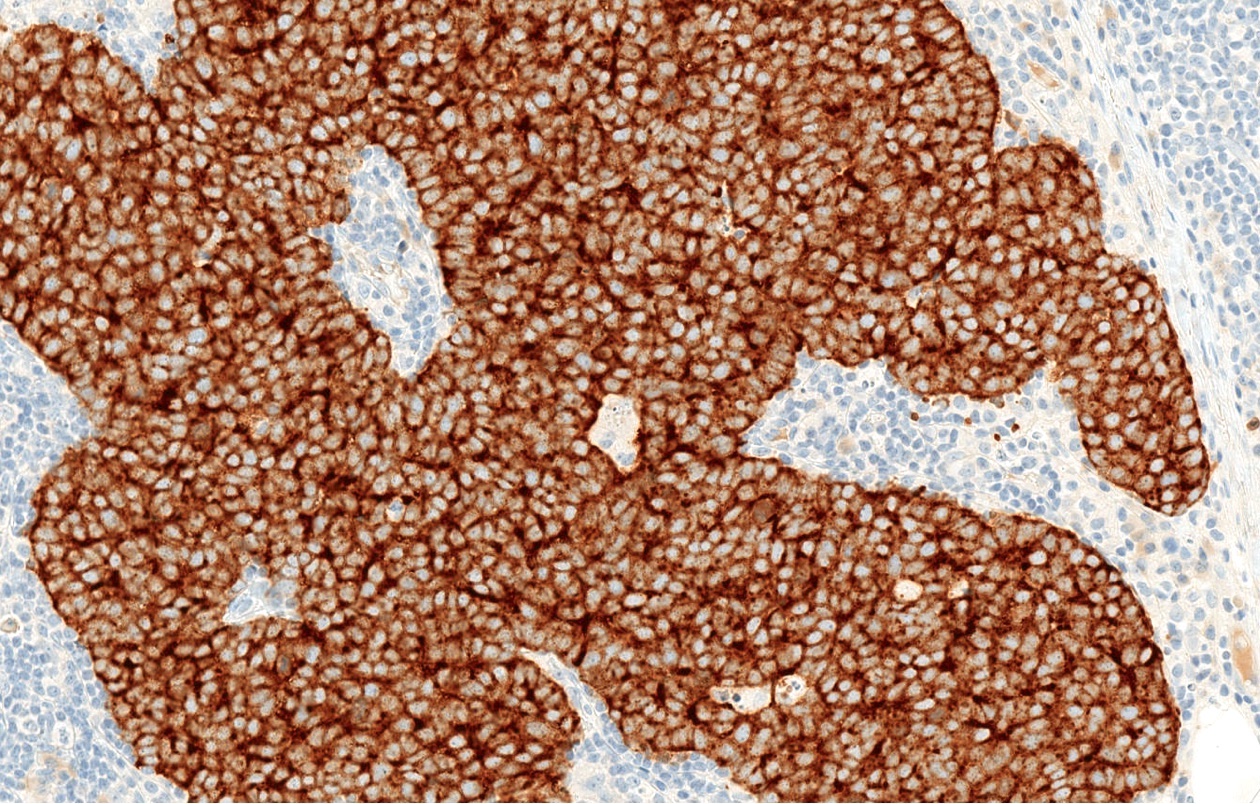

Microscopic (histologic) description

- Expansile, nodular or diffusely infiltrative tumor within the dermis, variably in subcutis

- Variable mixture of nodules, sheets, nests and trabeculae of neoplastic cells

- Generally, small round blue cell tumor with high N:C ratio, round / oval nuclei, finely dispersed chromatin (salt and pepper), indistinct nucleoli and scant cytoplasm

- Conspicuous mitoses and apoptotic bodies

- Variable nuclear molding and crush artifact

- Majority of cases display pure neuroendocrine morphology (pure Merkel cell carcinoma)

Microscopic (histologic) images

- Broad spectrum keratins: CAM 5.2, AE1 / AE3 (paranuclear, cytoplasmic or mixed pattern)

- CK20 (classic dot-like paranuclear pattern)